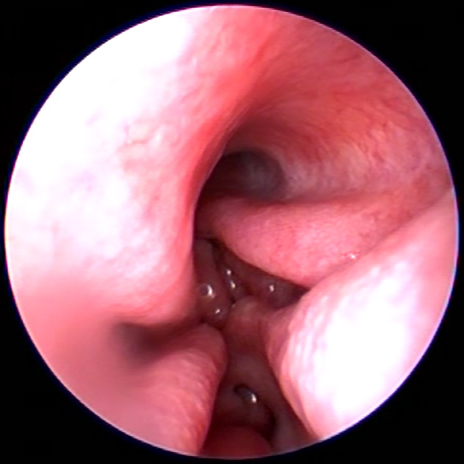

Diagnostiek

Het stellen van een diagnose kan soms net spoorzoeken zijn. Soms is het eenvoudig en soms is het lastig.

Onze diagnostische mogelijkheden hebben we uitgebreid door de aanschaf van vele soorten van apparatuur en het volgen van allerlei cursussen.